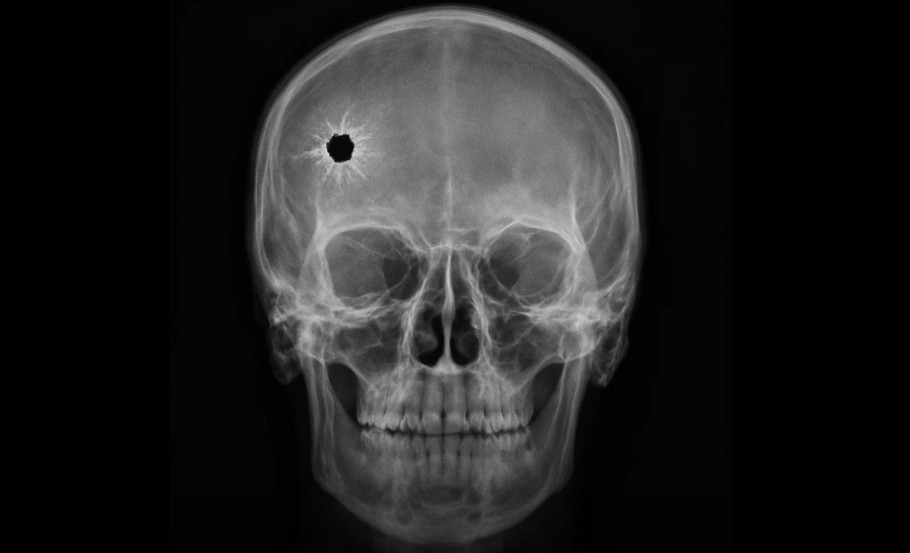

Glonțul din creier a stins obsesia: vindecare neașteptată în doar trei săptămâni

A supraviețuit, însă glonțul a rămas blocat în lobul frontal stâng, iar chirurgii nu au reușit să îndepărteze toate fragmentele.

Ce s-a întâmplat după această accidentare a fost, potrivit medicilor, extraordinar. În doar trei săptămâni, obsesiile și comportamentele compulsive aproape au dispărut complet.

Psihiatrul său, dr. Laszlo Solyom, a observat că leziunea pare să fi afectat o zonă cerebrală implicată direct în OCD, fără a deteriora funcțiile cognitive generale.